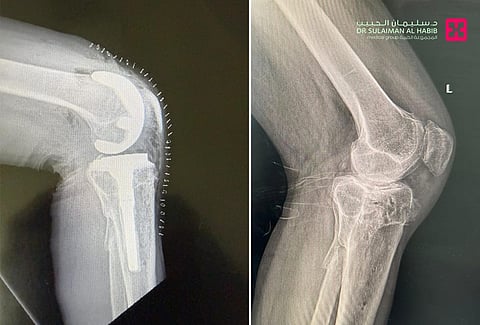

الذي قال أن المراجع وهو في العقد الخامس من العمر، جاء إلى المستشفى بسبب معاناته من خشونة متقدمة في مفصل الركبة اليسرى، نتيجة كسر قديم تم تثبيته بعملية رد مفتوح وتثبيت داخليORIF منذ سنوات طويلة. مضيفاً أنه خضع لفحوصات دقيقة أظهرت تغيّرات وخشونة بعد الكسر، مع تضيق في المسافة المفصلية وتصلب عظمي، وأجريت له عملية متقدمة تم فيها استبدال كلي للركبة باستخدام مفصل صناعي مزود بدعامة للساق، مطبوع بالتقنية ثلاثية الأبعاد بمساعدة الأشعة المقطعية، وجرت العملية تحت التخدير النصفي، انتهت ولله الحمد بالنجاح التام.

وأظهر المراجع تحسنًا واضحًا بعد العملية، إذ بدأ التحرك على قدميه باستخدام المشاية، والعلاج الطبيعي بعد ساعات من العملية، وفي خلال أيام قليلة وصل مدى الحركة من 0-120 درجة.

واستطرد أ. د. الجاسر قائلاً أن خشونة المفصل الناتجة عن الكسر تُعد من التحديات الجراحية الصعبة، حيث تصاحبها التشوهات وفقدان العظام والتغير في شكل المفصل الطبيعي. وغالباً ما تتطلب عمليات الاستبدال الكلي للركبة التقليدية تعديلات كبيرة أثناء الجراحة، لتحقيق المحاذاة الدقيقة، في حين أن تقنية الطباعة ثلاثية الأبعاد، تتميز بدقة أعلى في التطابق والمحاذاة، وتقليل زمن العملية الجراحية، وكذلك كمية العظم المزال أثناء الجراحة، إضافة إلى تسريع الشفاء وتحسن النتائج الوظيفية.